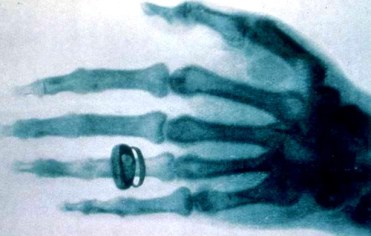

1895 – Wilhelm Röntgen discovers X-rays while experimenting with electricity and takes the first X-rays – X-ray Day *

Wilhelm Röntgen’s first X-ray